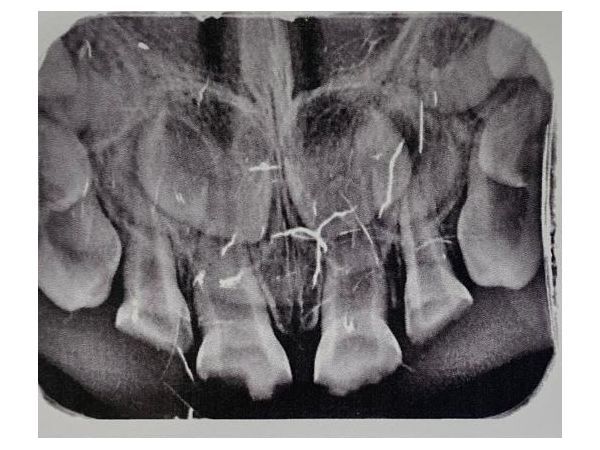

Инструментальное обследование удалось провести не сразу из-за беспокойства девочки, но в игровой форме ей всё-таки сделали компьютерную прицельную радиовизиографию:

- обнаружены очаги разрушения в коронковой части, которые сообщаются с полостями разрушенных зубов 5.2, 5.1, 6.1, 6.2;

- патологических изменений в периодонте не было.